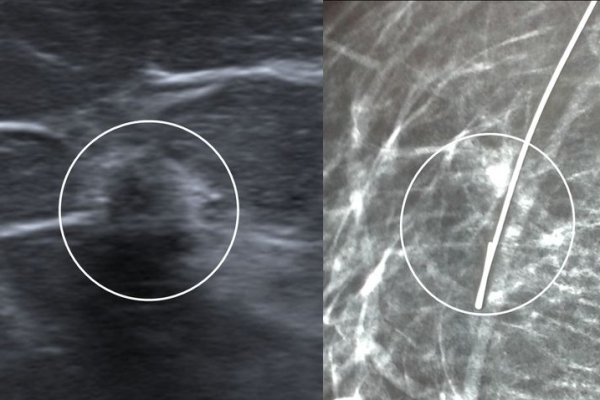

Σε περίπτωση που απαιτείται η χειρουργική αφαίρεση ενός ευρήματος που δε ψηλαφάται από το χειρουργό, τότε γίνεται η τοποθέτηση αγκίστρου σήμανσης (hook) λίγο πριν το χειρουργείο. Το άγκιστρο έχει σκοπό να καθοδηγήσει το χειρουργό για την αφαίρεση του σωστού τμήματος του μαστού, ώστε να αφαιρεθεί με ασφάλεια η ύποπτη βλάβη χωρίς να επηρεασθεί η αισθητική εικόνα του μαστού, πράγμα πολύ σπουδαίο ειδικά σε νέες γυναίκες και σε γυναίκες με μικρό μαστό.